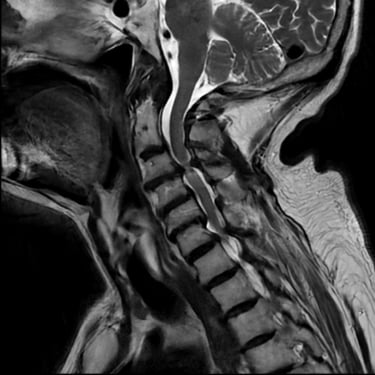

🧠Discitis Cervical con Absceso: Descompresión Cervical y Artrodesis.

La discitis cervical con absceso es una infección severa que puede causar compresión medular e inestabilidad. La descompresión cervical asociada a artrodesis permite drenar la infección, estabilizar la columna y preservar la función neurológica, favoreciendo una recuperación segura y progresiva.